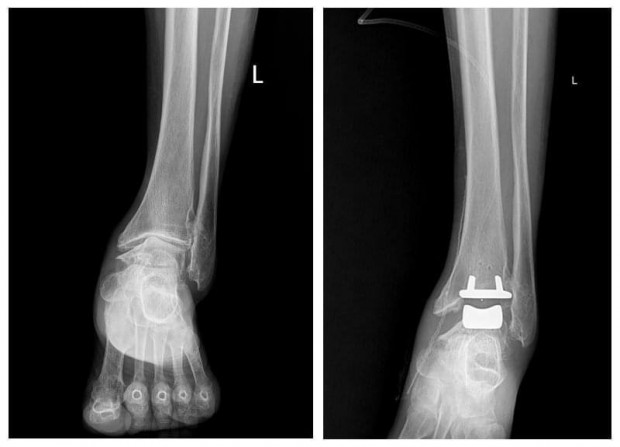

Гэмтэл согог судлалын үндэсний төвийн Насанд хүрэгсдийн мэс заслын тасгийн эмч, мэргэжилтнүүд шагайн хиймэл үе солих мэс засал эмчилгээг эх орондоо амжилттай нутагшууллаа.

ГССҮТ-ийн Насанд хүрэгсдийн мэс заслын тасгийн их эмч Ш.Баасансүрэнгээр ахлуулсан, тус тасгийн эрхлэгч Б.Баатаржав, Г.Бадамгарав нарын мэс заслын баг бүрэлдэхүүн шагайн үений хүнд хэлбэрийн артроз өөрчлөлтийн үед хиймэл үе суулгах мэс заслыг хийж, орчин үеийн дэвшилтэт мэс засал эмчилгээг тусламж үйлчилгээнд бүрэн нэвтрүүлээд байна.

Тус тасгийн хамт олон 2022 оны арваннэгдүгээр сард БНСУ-ын “Йонсей Гунвоо” эмнэлгийн захирал Eui Hyun Park болон бусад эмч, мэргэжилтнүүдтэй хамтран Монголд анх удаа шагайн хиймэл үе солих мэс заслыг хийсэн бөгөөд 2023 оны арванхоёрдугаар сараас эхлэн энэхүү мэс засал эмчилгээг бие даан амжилттай хийж буй юм.

Шагайн үений хүнд хэлбэрийн артроз өөрчлөлтийн үед хиймэл үе суулгах мэс заслыг Монголд нутагшуулснаар энэ төрлийн шалтгаант өвчлөл, зовиураар шаналж буй иргэд үйлчлүүлэгчид олон улсын стандартыг хангасан тусламж үйлчилгээг эх орондоо, бага зардлаар илүү хялбар, чанар хүртээмжтэй авах, амьдралын чанараа дээшлүүлэх зэрэг таатай боломж бүрдэж байна.